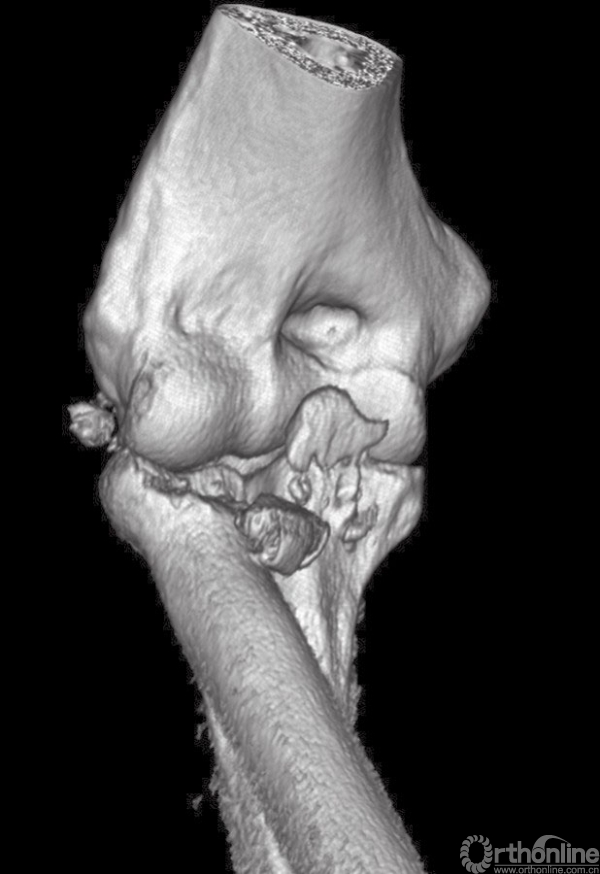

(2) 患者采用全麻、侧卧位,入路采用外侧入路,该入路便于切开复位、暴露肘关节、桡骨头重建和置换、固定冠状突以及后外侧韧带复合体的修复。外侧皮肤切口以肱骨外上髁为中心。前臂保持旋前位以增大骨间后神经与手术区域的距离。与单纯的桡骨头骨折采用的经肘肌和尺侧腕伸肌间的Kocher's间隔入路不同,对“恐怖三联征”患者可以利用损伤本身所造成的间隙进行暴露,而不需要特意的切开关节囊。损伤本身会导致关节囊、桡侧副韧带及大部分外侧肌肉软组织的破坏(图3)。

图3 三维CT显示肘关节脱位患者复位后为“恐怖三联征”